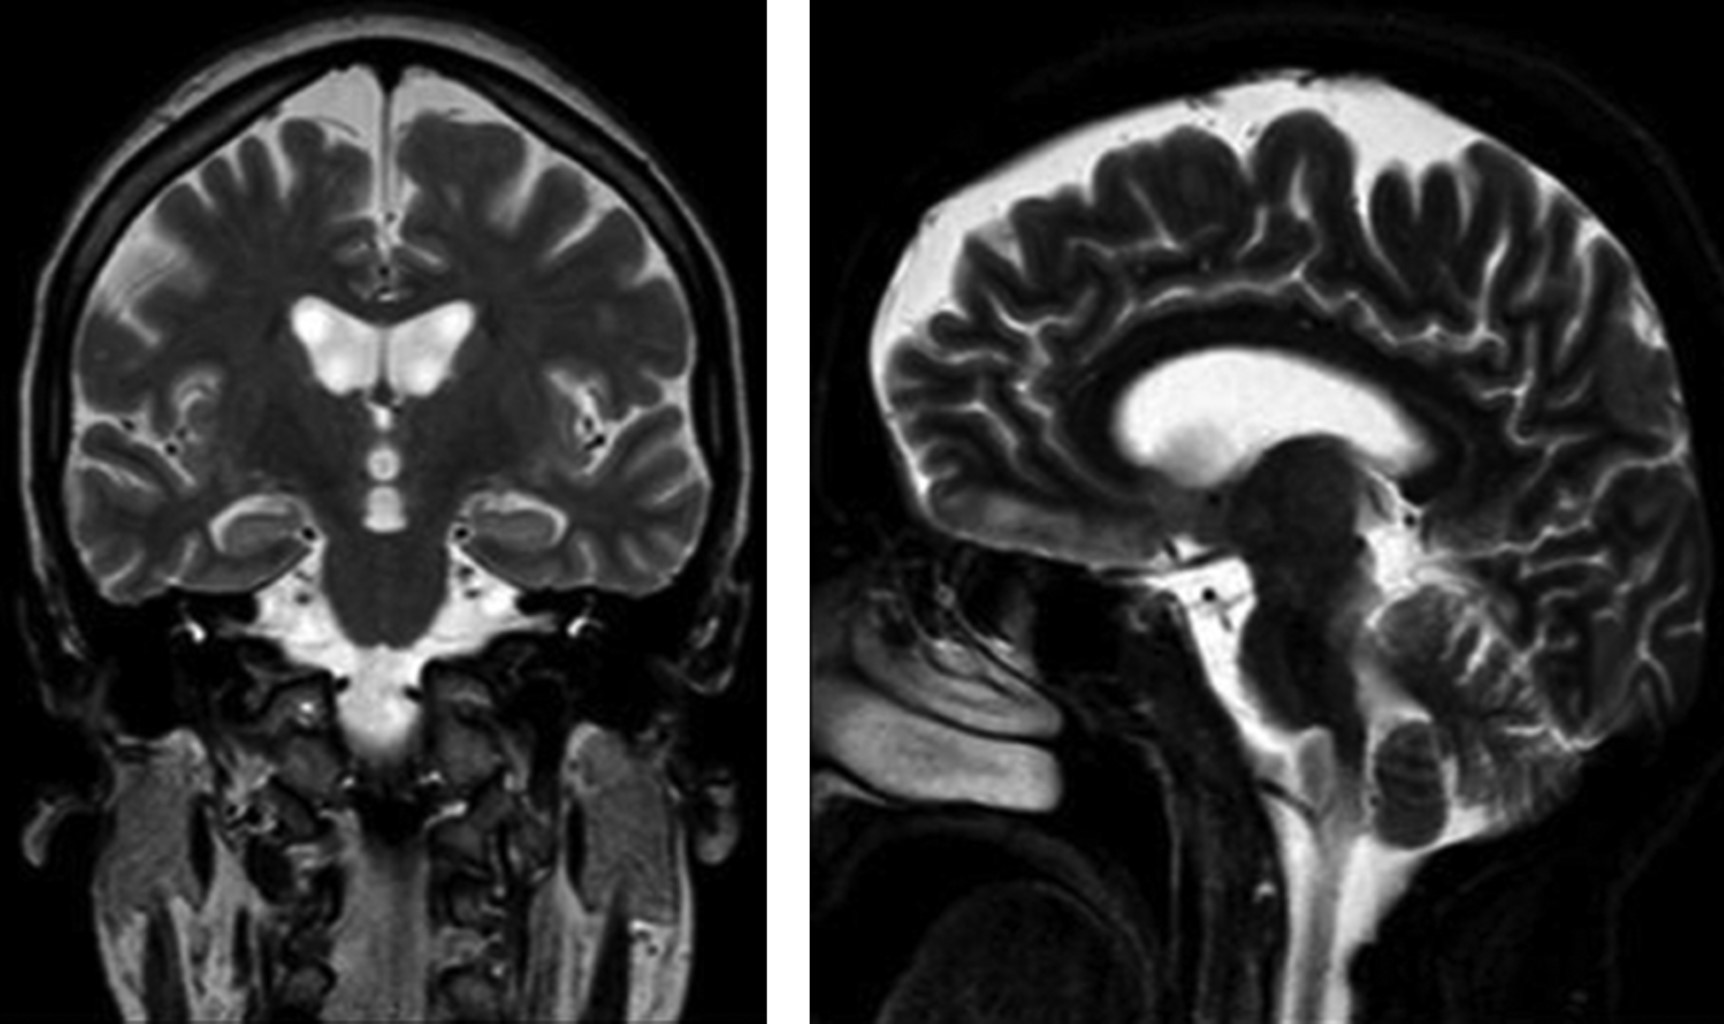

b) Evolución intrahospitalaria. Durante su estancia intrahospitalaria en psiquiatría continúa con la misma sintomatología, con desorientación en autopsíquica y alopsíquica (en función de tiempo y espacio), irritabilidad, agresividad, capacidad de concentración disminuida, funciones mentales no valorables, lenguaje incoherente, incongruente, ideas delirantes de daño y referencia, alucinaciones visuales, juicio desviado, pobre control de impulsos e intolerancia a la frustración. A la exploración neurológica se evidencia temblor intencional, disartria, ataxia cerebelosa, disdiadococinesia, apraxia ideomotora y del vestido, leve disminución de la fuerza en extremidades inferiores con alteraciones para la marcha. Exploración de pares craneales, reflejos osteotendinosos y función sensorial se encuentran sin alteraciones. El día 28 de septiembre del 2019 se reportaron niveles séricos de litio con 0.15 mEq/l. Se toma resonancia magnética con reporte del 15 de octubre, en el que se informa pérdida de volumen hacia la porción rostral de los lóbulos frontales y temporales de manera bilateral, sugestiva de atrofia cortico subcortical en esta región anatómica (Figuras 1 y 2). Posteriormente, el 18 de octubre se realiza electroencefalograma con resultado anormal, con signos de moderada alteración funcional cortico subcortical difusa con discreto predominio anterior bilateral.

Figura 1